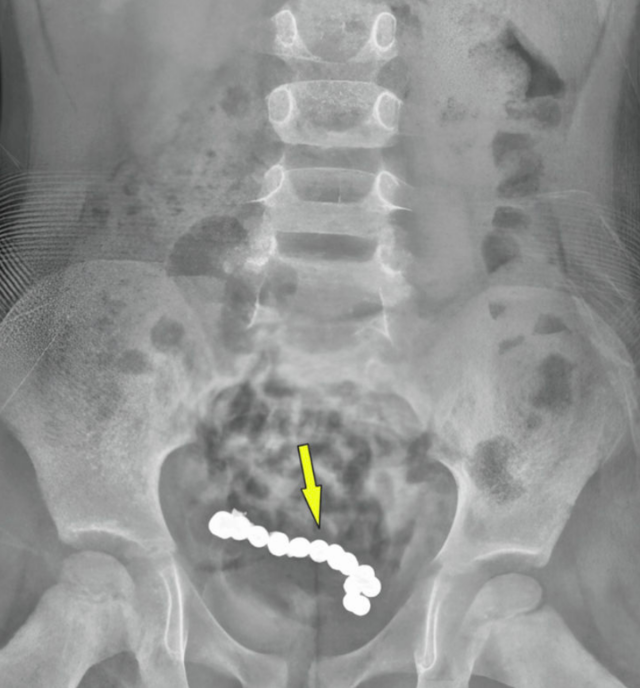

1년 동안 복통을 호소한 4세 남아의 뱃속에서 22개의 자석 조각이 발견돼 충격을 주고 있다. 큐레우스 캡처

그러나 증상은 호전되지 않았고, 이후 컴퓨터단층촬영(CT)으로 복부를 다시 촬영한 결과 하복부에 둥근 자석 여러 개가 사슬처럼 연결된 모습이 확인됐다. A군이 약 1년 전 자석을 삼킨 뒤 체내에 남아 있었던 것으로 추정됐다.